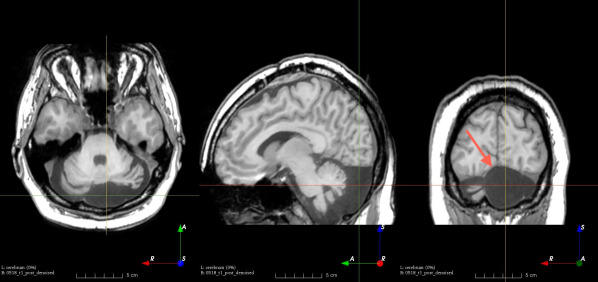

Refer to caption

(a)

(b)

(c)

(d)

(e)

(f)

(g)

(h)

Figure 6: Examples of challenging images for cavity segmentation. (a) Small frontal lesionectomy surrounded by hypointense white matter (b) Brain shift after contralateral temporal lobectomy (not shown) (c) Small frontal lesionectomy near the Sylvian fissure (d) Lack of boundaries between oedema and resection cavity (e) Possible blood clot within the cavity (f) Brain shift, oedema and resection cavity (g) Arachnoid cyst and resection cavity (h) Cerebellar degeneration. Green annotations represent areas that correspond to resection cavities; red annotations represent areas that do not.